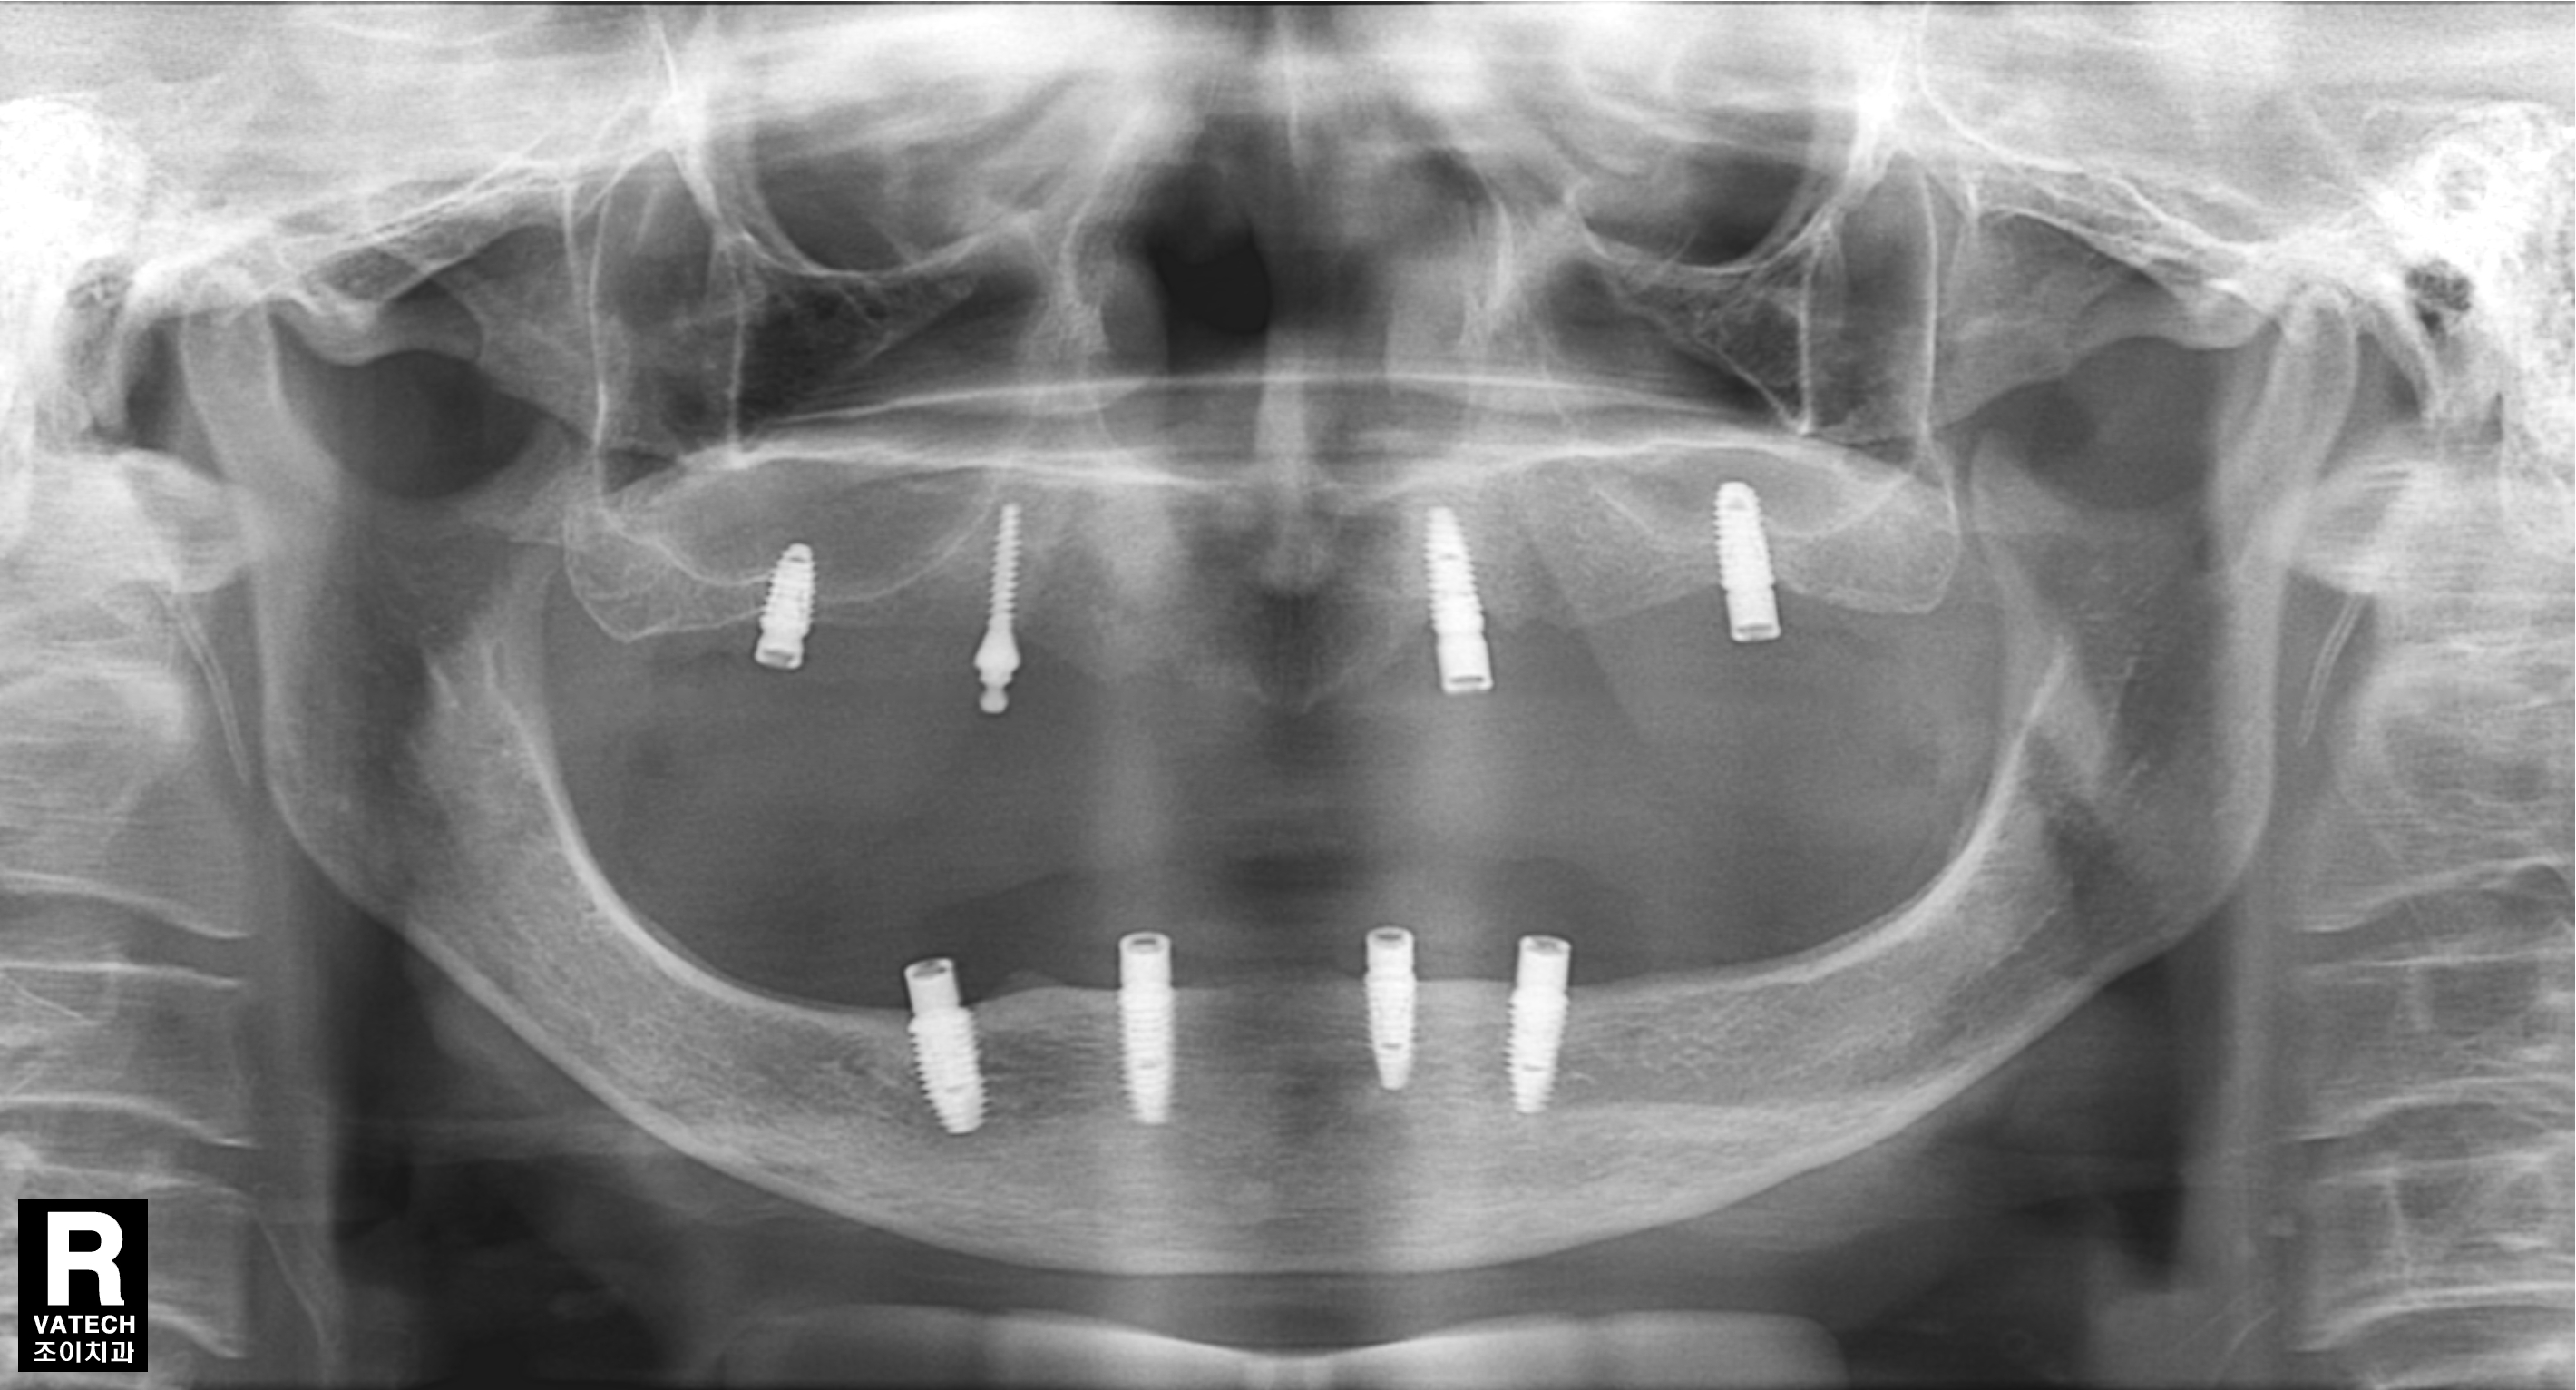

[임플란트] 제목 : 어테치먼트를 이용한 틀니치료

오래된 틀니 사용으로, 골흡수가 심하게 진행된 고령의 무치악 환자에서 어테치먼트를 이용한 틀니치료